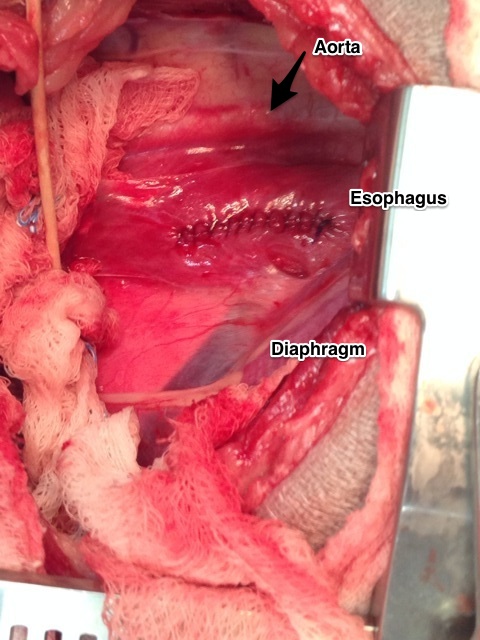

The standard treatment for a primary lung tumor is surgical removal. At this juncture (or earlier) your primary veterinarian may recommend that you consult with a board certified veterinary surgeon due to the intricacy of the procedure and the “around the clock” care your family member will require following surgery (if your veterinarian does not offer this service). Generally, surgical removal of the tumor is the standard of care for treatment of this disease. Smaller tumors can sometimes be removed by thoracoscopy (minimally invasive scoping of the chest), however a very experienced anesthesia team is need to provide one lung lobe ventilation to the pet. Usually the tumor is accessed by a lateral thoracotomy depending on the which side of the chest the tumor is located. The tumor is isolated and the affected lung lobe is removed (various techniques can be used). I prefer removal with a Thoracoabdominal (TA) stapling device. In all surgeries, a chest tube is placed for 12-24 hours following surgery.